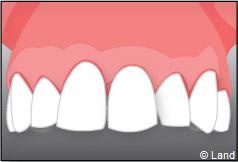

Exemple d’un implant unitaire pour remplacer une dent antérieure manquante.

Exemple de 3 dents manquantes remplacées par 3 couronnes sur implants.

Pose des piliers prothétiques et des 3 couronnes scellées.